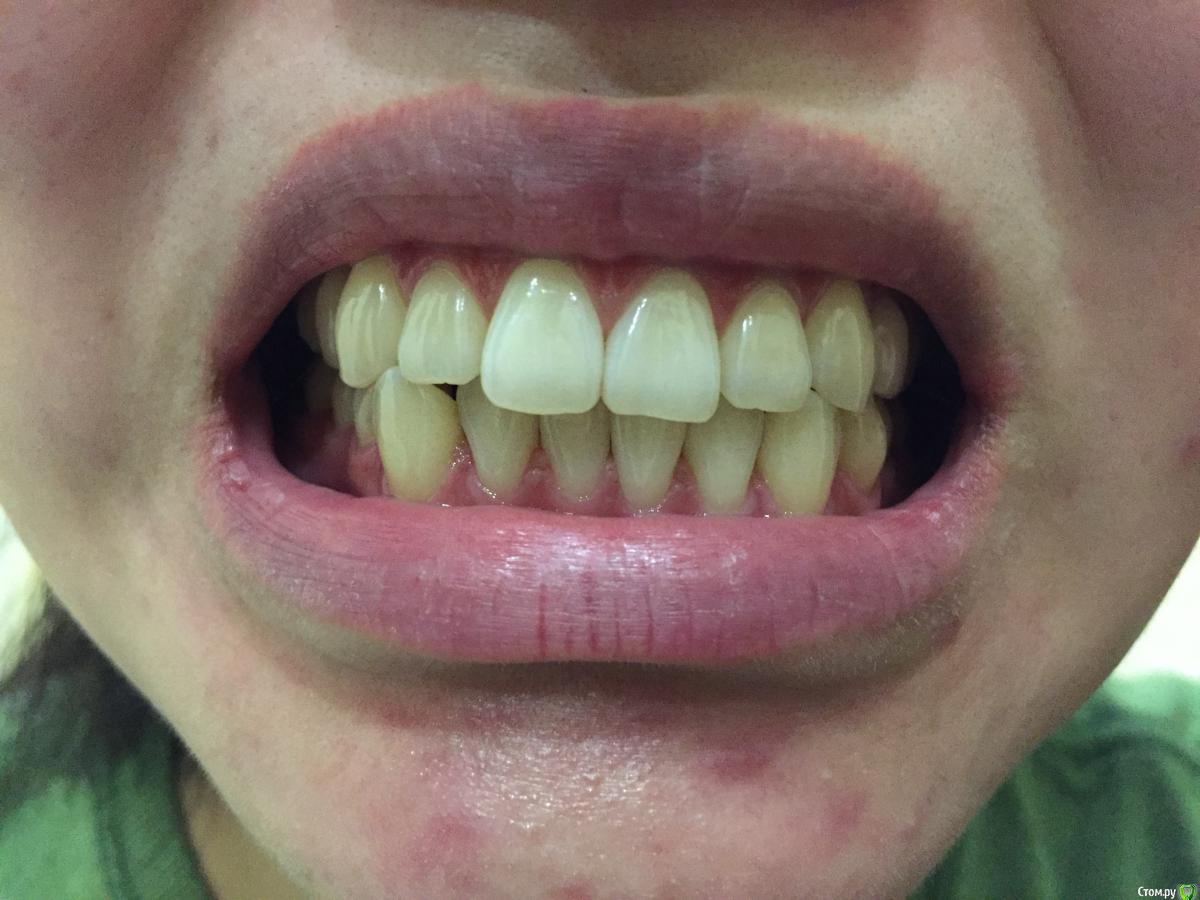

Помогите разобраться, мнения коллег разошлись.

Пациентке 21год, беспокоит 43 выдвинут вперёд, рецессия Десны у 14, 24.

1. Поставить брекеты, чтоб выровнять нижний ряд.

2. Удалить 48 и 28 и затем поставить брекеты

3. Ничего не делать, оставить так как есть.

высокая вероятность, что и на 1.2 рецессия в скором времени тоже будет.

не хватает еще хотя бы фото в прикусе справа и слева.